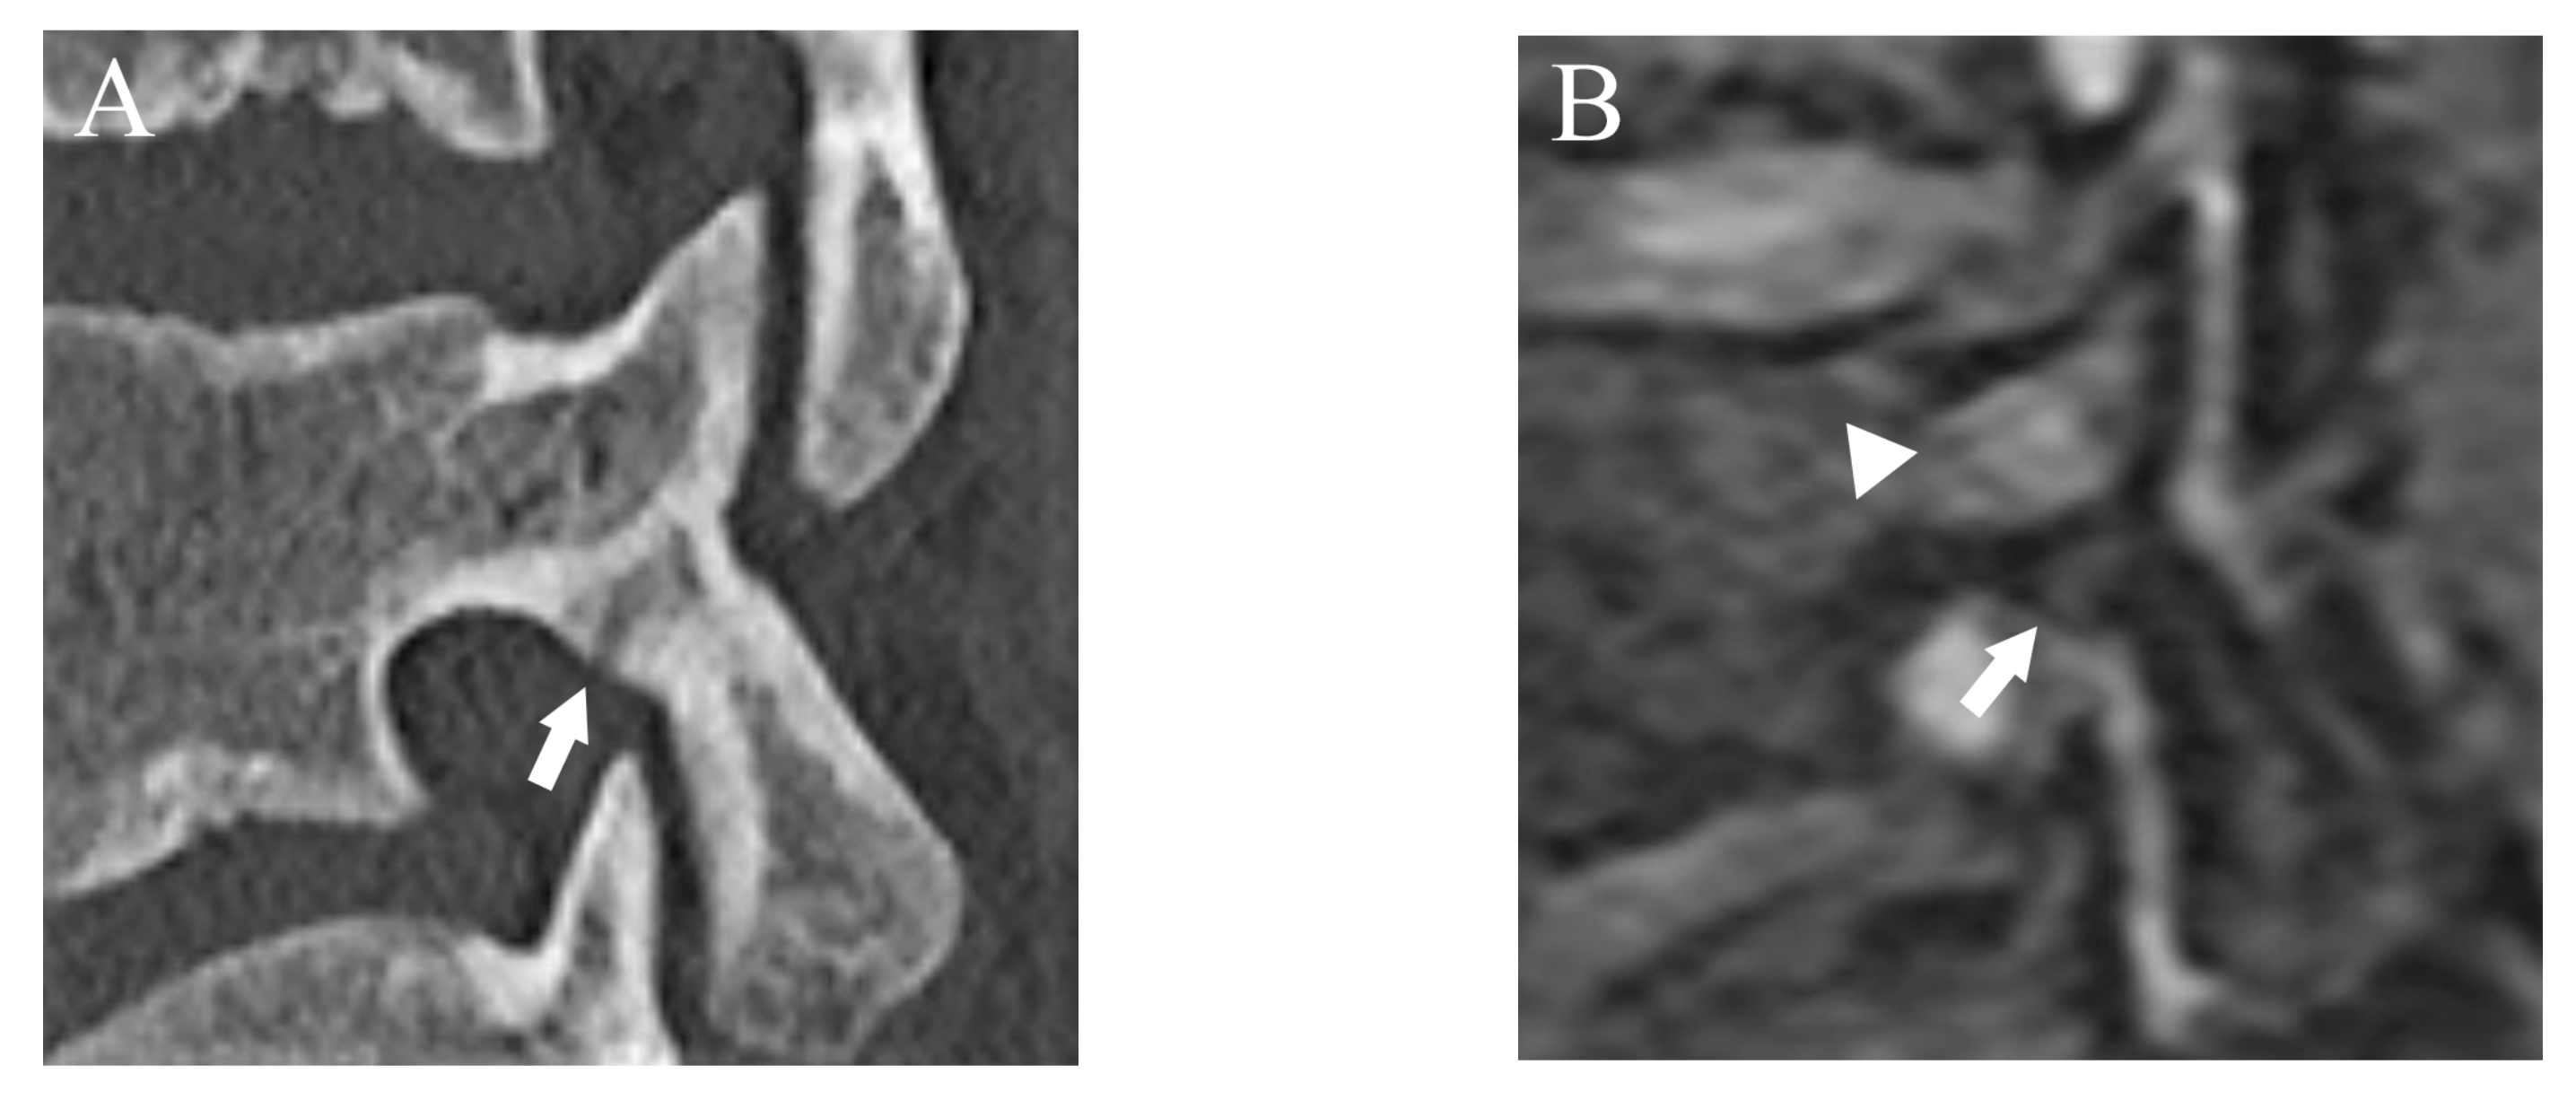

Figure 7.

The case that lower fracture grade was assigned by DESS than CT. (A) CT suggests an incomplete fracture which was consistent with grade 2 (arrow). (B) DESS shows a subtle high signal in the cortex of the pars interarticularis and evaluated as grade 1 (arrow). BME is also detected (arrowhead).

Agreement of fracture grading with CT showed excellent (Kappa = 0.90 (95% confidence interval (CI): 0.84, 0.96)) on DESS but T1WI showed substantial (Kappa = 0.67 (95% CI: 0.61, 0.73)) agreement. Compared to reference fracture grade created by CT, nine cases were assigned a lower grade by DESS, whereas three were assigned a higher grade (Figure 7).